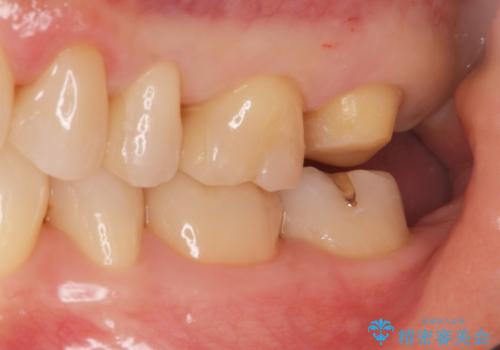

- 銀歯を無くしたいとの事で来院。

拡大鏡下でメタルを除去し虫歯がないことを確認してから白い詰め物、被せ物で治療を行いました。